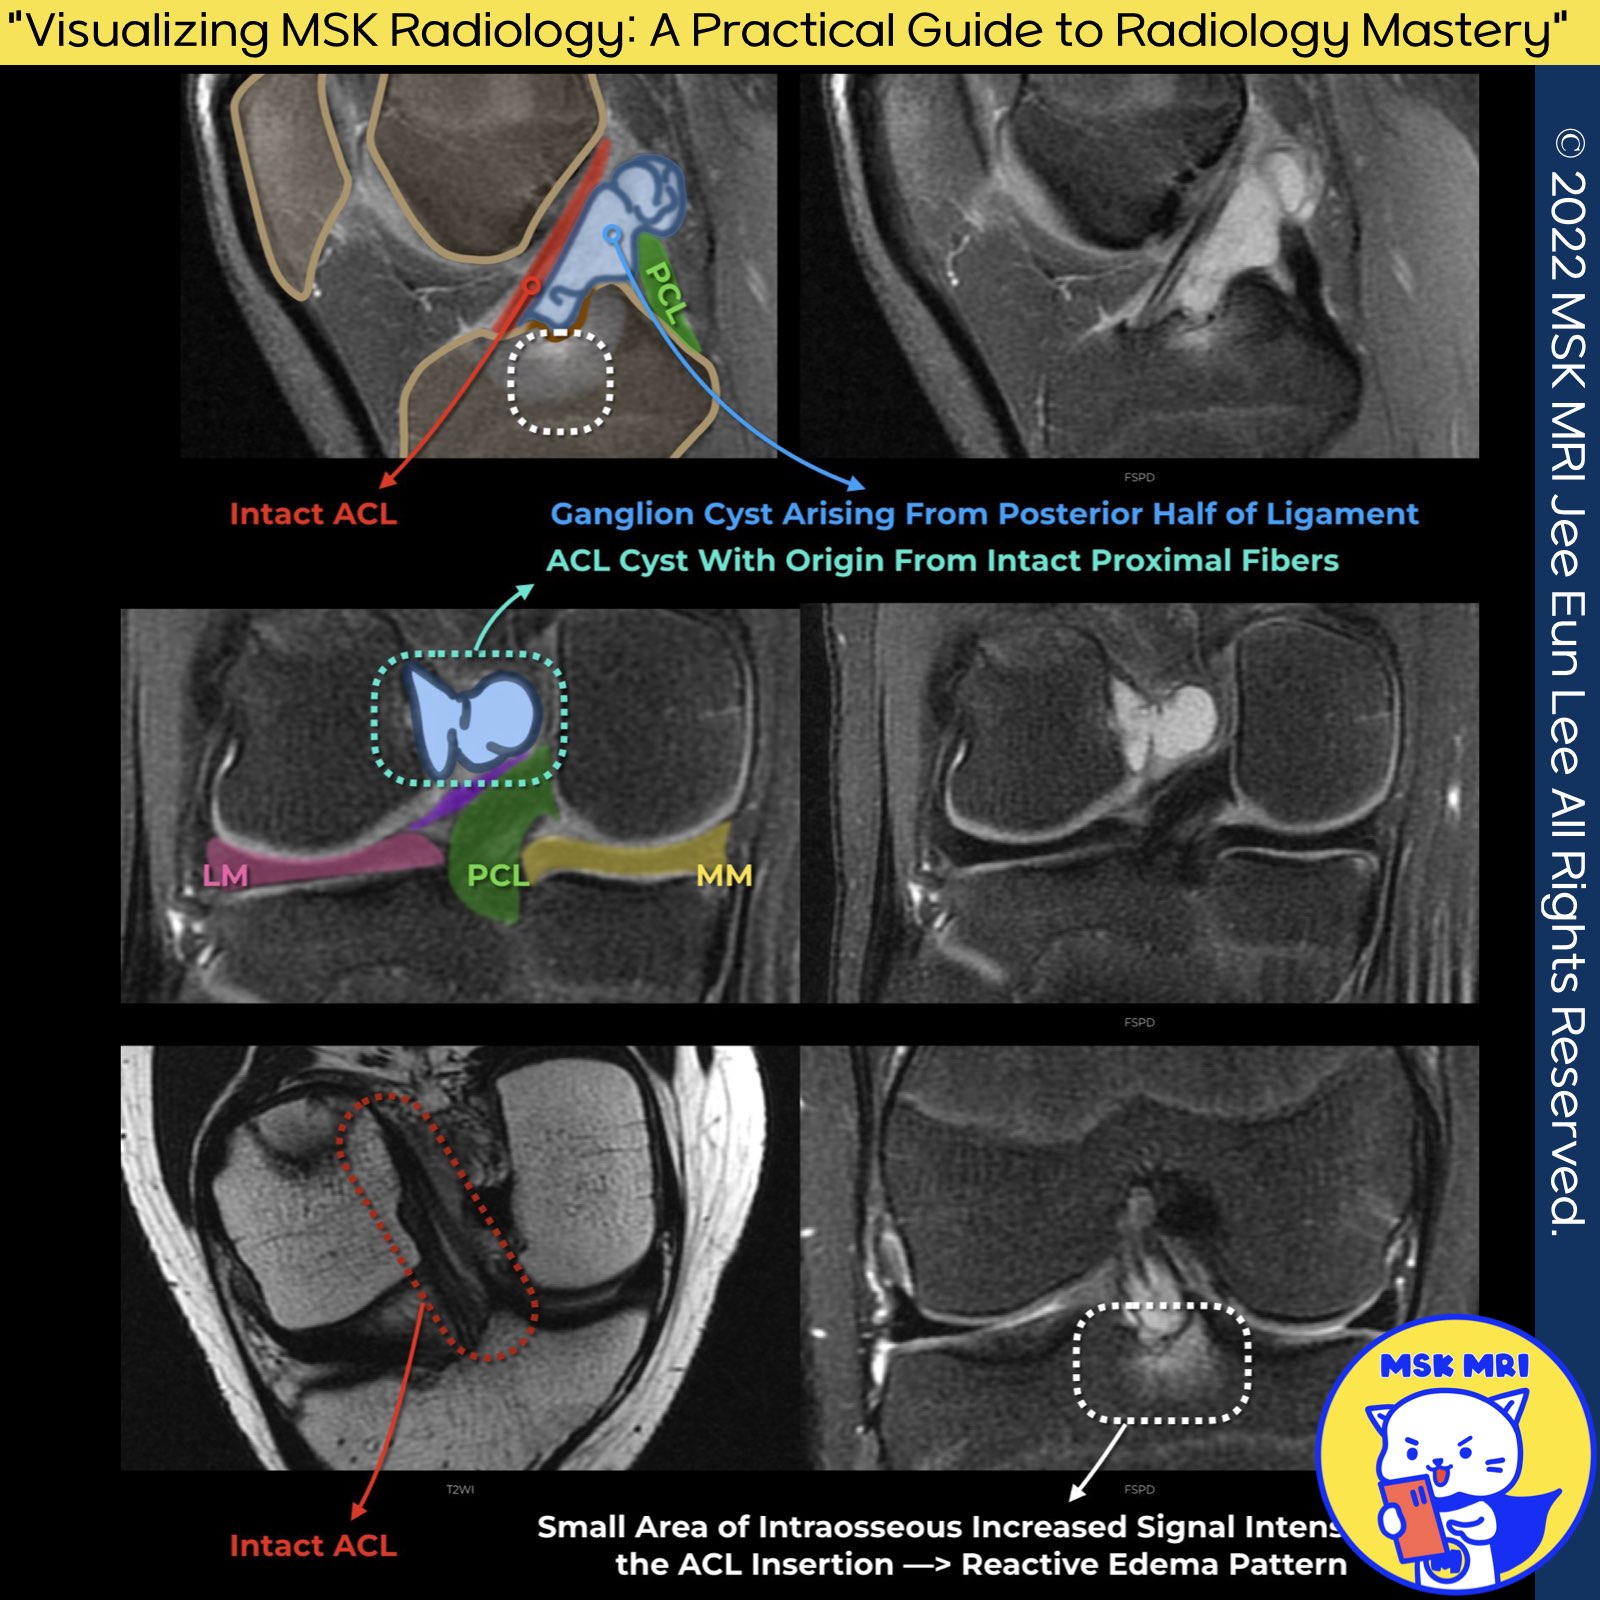

★ Cruciate or Intercondylar Notch Cysts ★

Intercondylar notch or ganglion cysts of the ACL, also known as cruciate cysts, are pathological formations that can arise both on the surface and within the Anterior Cruciate Ligament (ACL) substance.

These cysts are typically found in the middle and proximal portions of both the ACL and the Posterior Cruciate Ligament (PCL), highlighting their potential to affect critical structures within the knee joint.

📌 Pressure Erosion: The cysts may produce pressure erosion of the adjacent lateral femoral condyle, a condition that could be symptomatic and present with pain, especially during joint loading activities.

A potential association between these cysts and ACL injuries and other intraarticular joint pathologies indicates a need for careful diagnostic evaluation.

In some cases, cruciate or intercondylar notch cysts may present as incidental findings during imaging for unrelated conditions, suggesting a varied clinical significance.